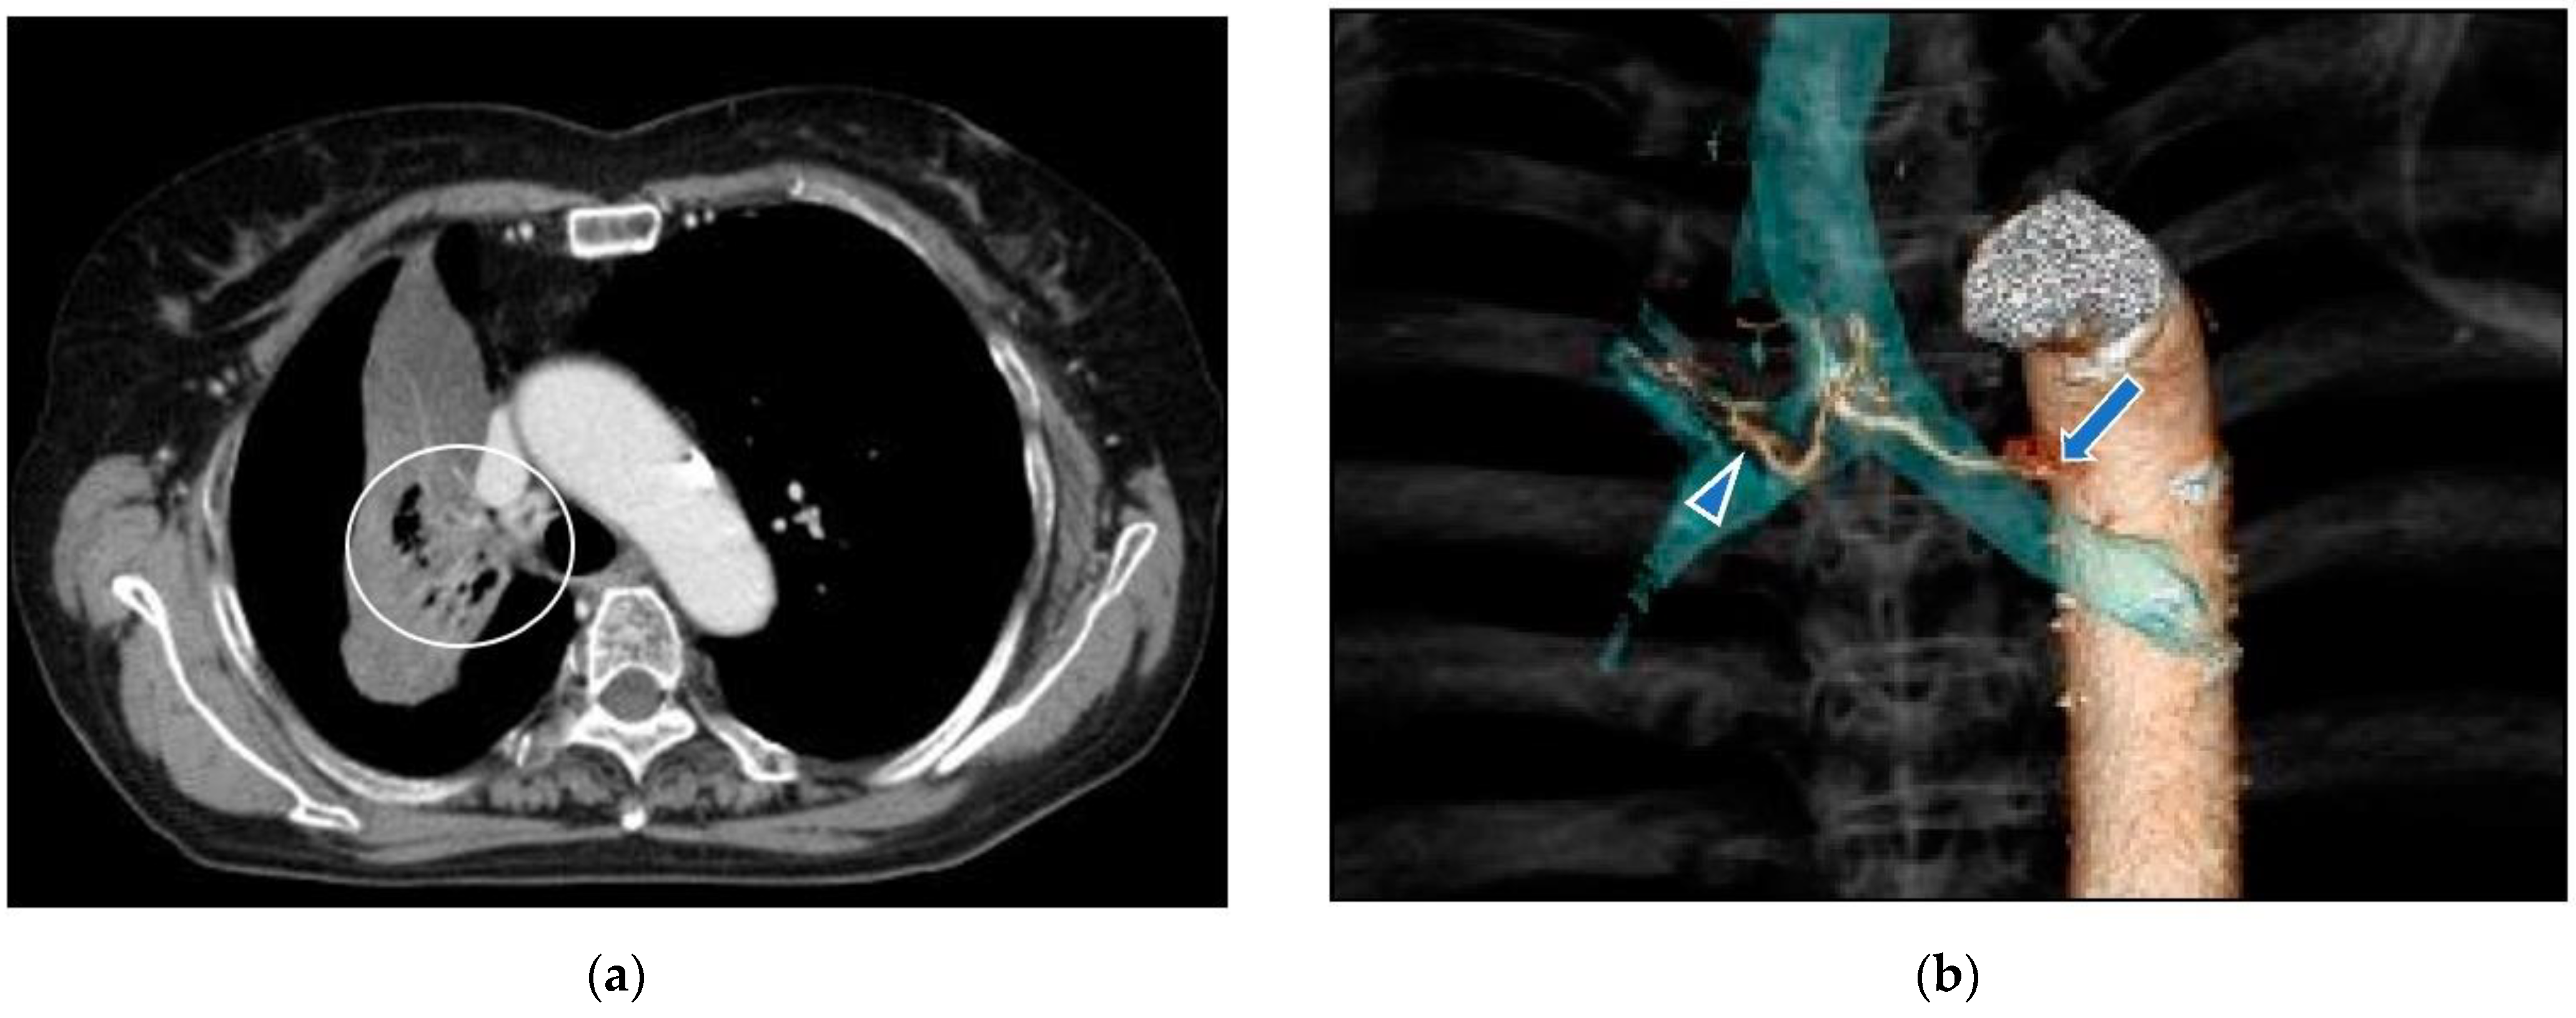

Case 2: A 75-year-old woman consulted our clinic complaining of severe cough (Figure 11). A Tumor located in the proximal part of the right upper lobe caused atelectasis of the right upper lobe. She had not undergone systemic chemotherapy due to her age and concomitant bronchiectasis. The first treatment through the bronchial arteries was carried out by infusing docetaxel; 20 mg, cisplatin; 20 mg, bevacizumab; 100 mg with embolization by 1.0 mg of fluorouracil loaded HepaSphere (50–100 micron). In total, 6 sessions of treatment have been repeated to maintain better QOL. The patient died from obstructive pneumonia 29 months after the initial treatments.

Complete disappearance of the target lesion was found and intrapulmonary metastases in the right lung were newly detected.

Figure 11. A 75-year-old female with right lung cancer. (a): A contrast-enhanced CT. The tumor (circle) around the right upper bronchus caused atelectasis of the right upper lobe. (b): A volume rendering 3D image demonstrates the common trunk (arrow) of the bronchial and intercostal artery. The right bronchial artery (arrowhead) distributes along the right upper bronchus. (c): Selective DSA of the right main bronchial artery. Abnormally dilated vessels were demonstrated around the right upper bronchus. (d): Angio-CT of the right bronchial artery. The tumor causing atelectasis of the right upper lobe was enhanced. (e): A contrast-enhanced CT in a month after the initial therapy. Shrinkage of the tumor was found and atelectasis was improved. (f): A contrast-enhanced CT in 20 months after the initial therapy. Six sessions of treatment were repeated in the same manner.